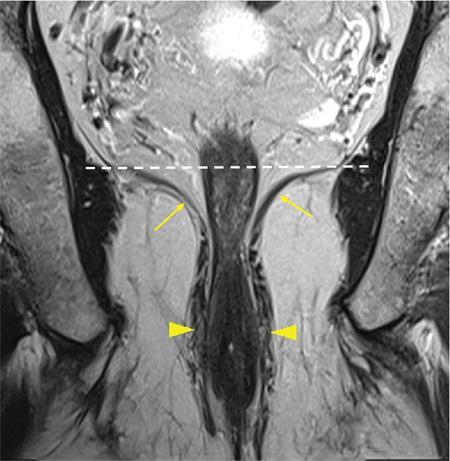

Sumit Mukhopadhyay, Saugata Sen, Aditi Chandra, Argha Chatterjee, Priya Ghosh, Anisha Gehani Cloaca is the part of hindgut caudal to the attachment of the allantoic diverticulum. It divides into a broad anterior urogenital (vesicourethral and urogenital sinus) part and a narrow posterior anorectal compartment/primitive rectum, separated by the urorectal septum. This anorectal compartment gives rise to mid rectum and lower rectum and upper part of anal canal proximal to dentate line. The peritonealized upper part of rectum develops from hindgut proximal to cloaca. The distal most part of anal canal below the dentate line develops from invaginated ectoderm known as proctodeum (Fig. 8.5.1). Initially during development, the rectum is suspended from the posterior abdominal wall by a mesentery, along with the rest of the gut. After completion of rotation of the gut, rectal mesentery fuses with the posterior abdominal wall, majority of rectum becomes retroperitoneal and hindgut mesentery is seen as mesorectum. The artery of the hindgut is inferior mesenteric artery. Anatomically, classically taken as 6 inches (approximately 15 cm), or beginning at the level of S3 vertebra. Surgically defined as 15–18 cm from anal verge (AV), thus anal canal and rectum are considered together for the purpose of surgical and radiological anatomy, though management differs in cases of rectal adenocarcinoma and anal squamous cell carcinoma (SCC). Various trials on rectal cancer neoadjuvant therapy have taken different lengths of cut-off for rectal cancer starting from AV: 9 cm, 12 cm, 15 cm or 16 cm (Table 8.5.1). Rectum continues as sigmoid colon superiorly. The point of transition between rectum and sigmoid colon is controversial. Anatomically, this is the point where sigmoid mesocolon ends, appendices epiploicae are lost and taenia coli gradually converge and disappear. There is no single transition point between these features. These features are not visible to the radiologist/endoscopist as well. Several features defining rectosigmoid junction/transition are variously accepted by different radiologists: Rectum continues as anal canal, which opens to the exterior at AV (mucocutaneous junction). Anorectal junction (ARJ) is considered to be the point at which the angle of the long axis changes, and corresponds to the upper border of puborectalis muscle. The change in axis of anal canal and rectum is well visualized on sagittal MRI. Dentate line lies along the anal crypts (the openings of anal glands), and vertical folds called columns of Morgagni extend superiorly from the dentate line. Anatomists consider the dentate line to be the landmark for ARJ, but the dentate line lies distal to the puborectal sling, and this definition is not clinically relevant. Anal canal is directed posteroinferiorly. At ARJ, the long axis of rectum changes so that it is directed anteroinferiorly. Mid rectum and upper rectum follow the sacral concavity, and the long axis of rectum is again directed posteroinferiorly. Upper rectum is frequently mobile and may not be in midline. Three incomplete folds consisting of mucosa, submucosa and circular muscles, named as Valves of Houston, are seen within the lumen of rectum during endoscopy, but these are not visualized radiologically. The middle valve is roughly at the level of anterior peritoneal reflection, and the superior most valve is at the level of rectosigmoid junction. Surgically and radiologically, rectum is divided into thirds: lower third, middle third and upper third (Table 8.5.2). Most commonly, this division is according to distance or length from AV. Lower third is 0–5 cm, middle third is 5–10 cm, upper third is 10–15 cm from AV (Fig. 8.5.6). Some radiologists define low rectum as 6 cm or less from AV, mid rectum as 7–11 cm and upper rectum as 12–15 cm. The justification of defining low rectum as 6 cm or less from the AV is that, management of most of the tumours at this location suffers from surgical challenges due to tapering of mesorectum and proximity of other pelvic structures. These tumours have a higher rate of CRM positivity, abdomino-perineal resection (APR) and permanent stoma, higher rates of recurrence and mortality, poor function of stoma after sphincter preservation. Another way of defining low rectum, surgical management of which differs from the upper two-thirds, is the portion lying distal to the proximal origin of levators at pelvic side wall. This definition was provided by the English National Low Rectal Cancer Development Programme (LOREC) and is best visualized in the coronal plane by a line joining proximal origins of levators at pelvic side walls (Fig. 8.5.7). ARJ is an important landmark in the management of rectal cancer. Distance between lower border of the tumour and ARJ is important for treatment planning. ARJ is defined as the point at which puborectalis fuses with the levator muscles, and the long axis of rectum changes from anteroinferior to posteroinferior at this point. Its upper extent begins few centimetres above the dentate line, and its length varies from 2–5 cm from AV. Histologically the proximal end of the anal canal is the point at which the columnar epithelium of the rectum becomes the transitional epithelium. Anal canal mucosa has several longitudinal columns, known as anal columns, which end at the dentate line. Below the dentate line the mucosa is smooth and transitions into skin at AV. Approximately at the level of dentate line, the internal anal sphincter (IAS) ends, and the smooth mucosa leads to the intersphincteric plane, distal to which the external anal sphincter extends up to the AV (Fig. 8.5.8). Upper third of rectum is anteriorly covered by peritoneum. Peritoneal covering gradually widens superiorly till it is covered by peritoneum on all sides at the level of sigmoid colon. The exact level of peritoneal reflection varies between individuals, and is quite often seen in axial and sagittal MRI. In axial T2-weighted MRI, a thin hypointense layer with V-shaped attachment to anterior rectal wall is seen representing the anterior peritoneal reflection. This is known as the ‘sea-gull’ sign. Mesorectum and mesorectal fascia (Fig. 8.5.10): lower two-thirds are surrounded by extraperitoneal fat and connective tissue known as mesorectum, which contains lymph nodes, nerves and blood vessels (descending branches of superior rectal artery and corresponding veins). Mesorectal fat is contained within a thin layer of fascia, known as mesorectal fascia (MRF). MRF separates mesorectal fat from extra mesorectal tissues of the pelvis. A relatively avascular plane of areolar tissue lies between MRF and parietal pelvic fascia, facilitating surgery. Importance: Assessment of structures within mesorectum is important for staging and prognostication of rectal cancer. Mesorectal node involvement is N disease. Tumour extension within mesorectal vessels is known as extramural vascular invasion (EMVI) and is thought to be associated with higher chances of vascular dissemination and distant metastases. MRF forms the boundary of the surgical excision plane in total mesorectal excision (TME) – the standard surgery for rectal cancers at present. It is important to understand the various fascial reflections of the pelvis in order to understand pathways of disease spread. The plane between the MRF and the pelvic fascias is the surgical plane. Posteriorly, covering the sacrum, presacral venous plexus and hypogastric nerves, lies the presacral fascia. It fuses with MRF inferiorly at the level of levator ani muscle. The space between presacral fascia and MRF is known as the retrorectal/rectosacral/pelvirectal space, and that between the sacrum and presacral fascia is the presacral space. The presacral fascia continues laterally as the parietal pelvic fascia which covers the lateral pelvic wall. It has two lamellae which encase the pelvic visceral nerves as they course forward from the sacrum to the anterior pelvic organs. The rectosacral fascia/Waldeyer fascia, called as rectosacral ligament by anatomists, is a thickening arising from presacral fascia and running forward to meet the MRF. This divides the rectosacral space into a superior and an inferior compartment, communicating with each other. In males, anteriorly, between the rectum and prostate-seminal vesicles, lies the rectoprostatic fascia/Denonvillier fascia. It is difficult to distinguish from the closely related MRF, and carries the hypogastric nerve and vascular branches to the prostate and male genital organs. In females, anterior to the MRF, lies the rectovaginal septum. According to most views, this septum consists of two layers. The anterior layer corresponds to Denonvillier fascia, and extends from the pelvic floor to the posterior wall of vagina and uterus. The posterior layer is in close relation to the MRF, runs from the pelvic diaphragm and ascends to the peritoneal reflection before fusing with the rectal wall. The lateral rectal ligaments are controversial structures as they are not visualized by imaging and may not carry important structures such as nerves and vessels. However, in some cases, the middle rectal artery may run through them and the accompanying lymphatics may provide a pathway between mesorectal and extra mesorectal lymph nodes. In females, the pelvic floor may be considered to have three compartments, anterior compartment containing bladder and urethra, middle compartment containing the vagina and the posterior compartment containing the rectum. These compartments are supported by the endopelvic fascia and levator ani muscle. The levator ani has several compartments, of which the two most important ones are the iliococcygeus and puborectalis. The iliococcygeus starts as the same fibres as the EAS, and then fans out as a sheet to insert at the pelvic sidewall at the tendinous arch. Posteriorly these fibres fuse in the midline to form the levator plate/raphe. The pubococcygeus and puborectalis are considered together as pubovisceralis muscle. It inserts lateral to the symphysis pubis anteriorly, and forms a sling around the rectum, pulling it anteriorly. Components of the levator ani can be identified in T2-weighted MR images. In males, there are two compartments, anterior containing bladder, urethra, prostate and seminal vesicles and the posterior compartment containing the rectum. Pubococcygeus consists of pubourethralis and puborectalis in males. In sagittal images, the pubococcygeal line is an important reference line, drawn from the inferior border of symphysis pubis to the last joint of the coccyx, representing the level of pelvic floor. The H line is drawn from the inferior aspect of the symphysis pubis to the posterior wall of the rectum at the level of ARJ. This represents the anteroposterior width of the levator hiatus, and upper limit of normal is 5 cm. The M line is the vertical descent of the levator hiatus, drawn as a perpendicular line dropped from the pubococcygeal line to the posteriormost aspect of the H line, and should measure maximum 2 cm. The angle of the levator plate and the pubococcygeal line is also measured. In axial images, the entire normal levator is of uniform thickness and homogeneous low signal intensity. Coronal images show intact iliococcygeus muscle which is convex upwards. The upper half of the anal canal proximal to the pectinate line, the IAS, the conjoint longitudinal coat and the rectum drain lymph upwards into the mesorectal nodes (Fig. 8.5.11) and then lymphatics follow the superior rectal artery into the inferior mesenteric group of lymph nodes. The lymph from these nodes is carried by the intestinal lymph trunk(s). Anal canal below the dentate line along with the EAS drains to the superficial inguinal nodes. Lymphatic vessels also travel with the median sacral artery and drain the puborectalis muscle before finally joining the internal iliac lymph nodes. The internal iliac lymph nodes drain into pre-aortic and paraaortic (lumbar) lymph nodes and efferents from the nodes form the lumbar trunks. The intestinal trunks and the lumbar trunks enter the abdominal confluence of the lymph trunks at the level of the L1–L2 vertebrae, called the cisterna chyli, and then ascend as the thoracic duct. The pelvic lymph nodes lying outside the mesorectum are termed as ‘extra mesorectal lymph nodes’. Above the dentate line: blood supply is from the superior rectal artery, which originates from the inferior mesenteric artery, a branch of abdominal aorta. Superior rectal artery passes in the sigmoid mesocolon and divides into two branches behind the rectum at the level of S3 sacral segment. The superior rectal artery ends in the anal columns by forming a rich vascular plexus/anastomosis with the branches of inferior rectal artery. Blood returns via the superior rectal veins into the inferior mesenteric vein, which drains into the splenic vein and eventually into the portal venous system. Below the dentate line, the inferior anal canal obtains its blood supply from the inferior rectal artery, which is a branch of internal pudendal artery, originating from the anterior division of internal iliac artery. Blood returns via the inferior rectal vein, which drains into internal pudendal veins, internal iliac veins and ultimately into the inferior vena cava (systemic circulation). Thus anal canal is a site of portosystemic anastomosis. Due to the venous anastomoses that occur in the anal canal and the backup of blood flow into the rectal veins, haemorrhoids may be present in patients with portal hypertension. A small part of muscular wall of rectum and anal canal is also supplied by median sacral artery, a direct branch of abdominal aorta arising at the bifurcation of aorta. Nerve supply: The inferior hypogastric plexus lies laterally on the surface of MRF on both sides. It receives sympathetic nerve fibres from the superior hypogastric nerves and parasympathetic ‘nervi erigentes’ from the laterally situated sacral nerves (S2–S4). Laterally, inferior rectal branches of the pudendal nerves and internal pudendal arteries cross the ischio-anal fossa to supply the external sphincter and anal mucosa. T2-weighted small FOV images reveal the layers of rectal wall and details of perirectal soft tissue and pelvic floor most accurately. For adequate assessment of the integrity and involvement of different layers, axial images are needed, which should be obtained perpendicular to the axis of the rectum in that segment. Angle of acquisition should be altered according to the change in axis of rectum (Fig. 8.5.12). The layers of rectal wall from inside to outside are (Fig. 8.5.10): When examining the anorectum with a radial scanning echoendoscope, the internal and EASs can be seen as two distinct rings. The inner hypoechoic ring of tissue represents the IAS the outer hyperechoic tissue ring represents the EAS. The thickness of normal IAS is 2–3 mm, and for EAS: 7–9 mm. The IAS becomes thicker and more hyperechoic with age, while the EAS tends to become thinner with age. Endoscopically, rectum begins at the dentate line and extends to 15–20 cm from the AV. The normal five-layer appearance of rectal wall in EUS is as follows: Imaging in the rectum and anal canal region is mainly for staging of tumours. The most common neoplasm of this region is rectal cancer and preoperative imaging evaluation is required not only for staging early and advanced disease but also for assessing response to treatment and for surgical planning. The techniques described here will mainly pertain to rectal and anal neoplasms. Plain radiographs have a limited role in the evaluation of rectal neoplasms. Primarily, it may be used as a modality in the emergency setting when patients come with constricting colorectal strictures causing large bowel obstruction. Radiographs of the abdomen in supine and erect positions are performed to look for features of bowel obstruction, air-fluid levels and free air under the domes of diaphragm in case of perforation, respectively. Conventional luminal contrast study is now obsolete for diagnosis of tumours in the rectum and anal canal and have been replaced by cross-sectional imaging. Sinogram studies with diluted iodinated contrast have been performed to detect extent of rectal fistulae. Endorectal Ultrasound (ERUS) can differentiate between the layers of the rectal wall and helps detect and stage tumours within the different layers of the rectum. ERUS can view the rectal mucosa in 360 degrees. The layers visualized include rectal mucosa, muscularis mucosa, submucosa, muscularis propria and area between the muscularis propria and perirectal fat. The role of ERUS in rectum is primarily in staging and in posttreatment surveillance of rectal adenocarcinoma. Staging of early tumours requires an ERUS due to its superior diagnostic performance for differentiating T1 from T2 tumours in comparison to other cross-sectional imaging modalities like MRI. As far as surveillance is concerned, endoscopy is mandated as it can detect early asymptomatic recurrences which improves overall survival (OS). This is substantiated by multiple recent meta-analyses in literature. Hence, even for patients on ‘watchful waiting’ as a treatment option after chemoradiotherapy, it is imperative to perform a DRE, EUS, CEA and correlate the findings with restaging MRI. The various recommendations for postoperative surveillance for rectal cancer using endoscopy are enumerated in Table 8.5.3. ASCO: American society of clinical oncology; ESMO: European society for medical oncology; NCCN: National comprehensive cancer network; USMSTF: United States Multi-Society Task Force. Drawbacks include heterogeneity in operator skill and operator dependency as well as inability to pass stenosing lesions. Poor depth of penetration of the probe results in reduced visualization of the mesorectal fat, limited assessment of pelvic side walls and EMVI and reduced diagnostic accuracy for asserting involvement of CRM. Multidetector CT (MDCT) is the primary imaging modality used for rapid evaluation of not only bowel pathologies (luminal or mural) but also for evaluation of surrounding structures such as vessels, lymph nodes and mesentery. The ability to obtain high-quality clinical images through multiplanar reconstructions make it one of the most robust examinations for the initial evaluation of most bowel related pathologies. A routine abdominal CT scan would include acquiring a noncontrast axial image, followed by a portal phase image (at 70–90 seconds). However, for more detailed evaluation of solid organs, a general imaging dataset would include an unenhanced CT, followed by arterial phase (20–30 seconds), portal venous phase (70–90 seconds) and a delayed phase at 3 minutes. Many centres around the world omit the noncontrast scan to reduce radiation exposure. Lesions such as large tumours, pelvic nodes, collections and diverticulosis can be detected by contrast-enhanced CT. CT provides a more holistic evaluation and demonstrates possible complications of tumours such as obstruction, transition point and perforation that may not be clinically evident. However, accurate detection and staging of tumours in the rectum is better performed by MRI. Like TRUS, MRI can depict the layers of the rectal wall with high resolution, especially when performed at 3 Tesla and with an endorectal coil. Although use of endorectal coils may provide improved diagnostic accuracy for T stage as compared with phased-array coils alone, it is known that endorectal coils increase patient discomfort and may account for increasing motion artifacts. Insertion of such coils is also not possible in case of stricturous lesions. Performance of high-resolution imaging using phased-array MRI coils at 1.5 or 3 Tesla, as was used in multicentre trials was excellent. MRI technique and image quality play a critical role in evaluation of rectal cancers, and accuracy is dependent on obtaining high-resolution images that are perpendicular to the plane of the tumour. Particular note is to be made whether the tumour is mucinous or nonmucinous as the former have worse prognosis and higher tendency to metastasize. For technical aspects of MRI, it is recommended by ESGAR that bowels and bladder are emptied. Rectal distension is not indicated as it stretches out the CRM. Minimum slice thickness for such scans is 3 mm. DWI is essential for both primary staging and restaging. Microenemas may be considered to remove air from the rectum and reduce artifacts in DXI sequence. High-risk MRI features for distant metastases include EMVI, mesorectal tumour depth >5 mm, T4 stage, involved circumferential resection margin (CRM). In addition to initial staging prognostic features, MRI also helps in assessing response to neoadjuvant therapy which is also an indicator of survival and chances of recurrence. MRI is sensitive in detecting the presence of lymph nodes but remains nonspecific for differentiation malignant from benign nodes with high diagnostic certainty owing to the presence of micrometastasis even in small-sized nodes (up to 5 mm). Contrast administration is not recommended. Drawbacks of MRI include reduced diagnostic accuracy for identifying early rectal T1 and T2 tumours, and to sometimes differentiate T2 from early T3 lesions. Increased scan times in the elderly and cost may also be constraints in some settings. Virtual colonoscopy can help in identifying primary and synchronous colonic lesions. CT Colonography (CTC) is beneficial after incomplete colonoscopy (due to nonpassable stricture) to evaluate the remainder of the colon. CTC is advocated as a screening test for colonic polyps and colon cancer in vulnerable populations. It has a sensitivity of 93% and a specificity of 97% for detecting polyps >1 cm. MRI scores over all modalities in the local staging of rectal neoplasms. The more common application of PET-CT is in identifying nodal and distant metastases in rectal adenocarcinoma, melanoma and lymphoma. Limitations of PET include poor sensitivity in detecting small (<10 mm) colonic lesions and decreased fluorine-18-2-fluoro-2-deoxy-D-glucose uptake by mucinous tumours. For rectal melanoma, MRI may be performed along with a whole body PET-CT scan for regional and overall staging. Rectal lymphoma does not require local staging and a whole body PET-CT is generally acceptable as the imaging modality of choice. MRI is the imaging modality of choice due to better delineation of the extent and involvement of the anal sphincters. The inguinal nodes are regional nodes in anal cancer and this region is covered in the scan. The most common rectal tumour is rectal cancer. It is also one of the most common malignant neoplasms and the second most frequent cancer occurring in the large bowel. Majority of the patients are in the fifth to seventh decade. However, the incidence of rectal cancer has been on a rise in the younger population. Adenocarcinoma is the commonest histopathologic type of rectal cancer. Other than adenocarcinoma, several other neoplastic lesions also occur in the rectum, but are relatively uncommon (Table 8.5.4). Diagnosis of rectal cancer begins with physical examination/DRE followed by colonoscopy/sigmoidoscopy and biopsy from the mass (see figure below). If malignancy is confirmed on histopathological examination, imaging for staging is ordered (Fig. 8.5.14). MRI is the preferred method for locoregional staging. During staging of early tumours, ERUS also plays an important role. Majority of the guidelines (SAR and ESGAR) accept MRI as the modality of choice for locoregional staging and restaging after neoadjuvant treatment. CT thorax and abdomen is performed for metastatic evaluation. PET-CT is not routinely recommended in metastatic evaluation. ESMO guidelines outline the following indications for PET-CT: (1) If carcino-embryonic antigen (CEA) is high on presentation (2) Extensive EMVI. MRI of the liver may be recommended to evaluate any suspicious or equivocal lesions that are detected on CT scan. Therefore routinely pelvic MRI for locoregional evaluation and CT thorax and abdomen for metastatic evaluation is performed (Table 8.5.5). Based on the investigations, the rectal cancer is staged according to the latest AJCC classification (Table 8.5.6). T0 No evidence of primary tumour Tis Carcinoma in situ T1 Tumour invades submucosa T2 Tumour invades muscularis propria T3 a b c d Tumour invades subserosal tissue and perirectal tissue a <1 mm b 1–5 mm c >5–15 mm d >15 mm T4 a b Tumour invades peritoneum or other organs Tumour penetrates visceral peritoneum Tumour invades other adjacent organs or structures NX Regional lymph nodes cannot be assessed N0 No regional lymph node metastasis N1 a b c Regional lymph node metastasis (1–3 nodes) 1 lymph node 2–3 lymph nodes Tumour deposits in subserosa, mesentery/nonperitonealized perirectal tissues (cannot be differentiated from nodes on imaging) N2 a b Regional lymph node metastasis (>4 nodes) 4–6 node >7 nodes M0 No distant metastasis M1 a B c Distant metastasis Metastasis in one (1) organ Metastasis in more than one organ Metastasis to the peritoneum with/without other organ involvement Once the diagnosis is confirmed and staging investigations are completed, management is usually decided in multidisciplinary team meetings consisting of Surgeon, Radiation oncologist, Medical oncologist, Pathologist and Radiologist. The treatment protocols differ in the United States and Europe (Fig. 8.5.15). The different types of rectal surgeries are enumerated in the Table 8.5.7 and depicted in Fig. 8.5.16. Concept of use of neoadjuvant short course RT, long course RT with chemotherapy and chemotherapy only is a rapidly evolving field. Radiologist should be aware of the protocol used in their institution. A subset of patients (10%–23%) was found to have complete pathological response (pCR) in the postsurgical pathological specimen. There is significant evidence of prediction of pCR on presurgical MRI. Considering the ability of MRI in prediction of pCR, Prof. Habr-Gama and her group suggested the possibility of organ preservation in these patients. Hence ‘watch and wait’ policy came into vogue. In the subgroup where MRI predicts complete response, surgery can be avoided and patients may be followed up every 8–12 weeks using DRE, proctoscopy/sigmoidoscopy and MRI. Both T2W and DWI are used in MRI for prediction of complete response as well as for follow-up for prediction of recurrence. Close follow using the above-mentioned protocol ensures early detection of recurrence and hence treatment. Thus, MRI plays an important role in personalized treatment of rectal cancer. MRI plays an important role in rectal cancer management: During initial staging MRI helps in: In restaging after NACT, MRI helps in: Therefore good-quality high-resolution rectal MRI is required for accurate locoregional staging. Technique and protocol of MRI is summarized in the Tables 8.5.8 and 8.5.9. 1.5T-3.0T magnet strength High resolution T2w sequences Small FOV images Axial and coronal images – parallel and perpendicular to the rectal tumour For low rectal tumours coronal images –perpendicular to the anal canal